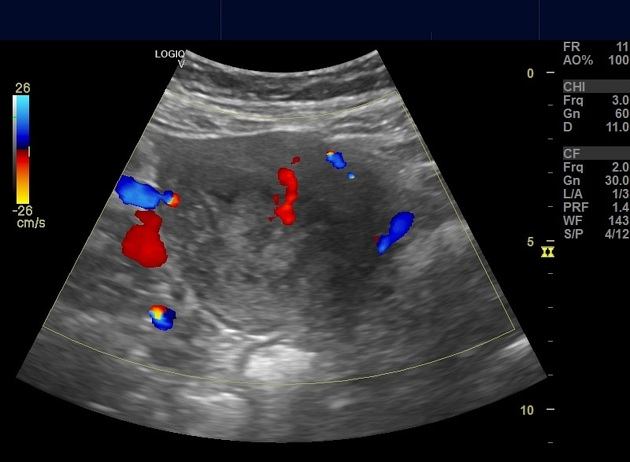

Polyp nội mạc tử cung

» Thông tin: Nữ giới – 40 tuổi.

» Lâm sàng: Rong kinh.